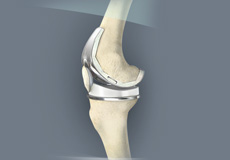

Total Knee Replacement

Total knee replacement, also called total knee arthroplasty, is a surgical procedure in which the worn out or damaged surfaces of the knee joint is removed and replaced with an artificial prosthesis.

Knee Implants

Knee implants are artificial devices that form the essential parts of the knee during a knee replacement surgery. The knee implants vary by size, shape, and material. Implants are made of biocompatible materials that are accepted by the body without producing any rejection response. Implants can be made of metal alloys, ceramic or plastic, and can be joined to the bone.